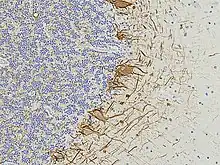

A formalin fixed and paraffin embedded section of human cerebellum stained with an antibody to neurofilament light, NF-L revealed with a brown dye, cell nuclei are revealed with a blue dye. Nuclear rich region at left is granular layer, region at right is molecular layer. The antibody binds processes of basket cells, parallel fiber axons, the perikarya of Purkinje cells and various othe axons. Image courtesy of EnCor Biotechnology Inc.

Neurofilament antibodies are also commonly used in diagnostic neuropathology. Staining with these antibodies can distinguish neurons (positive for neurofilament proteins) from glia (negative for neurofilament proteins).